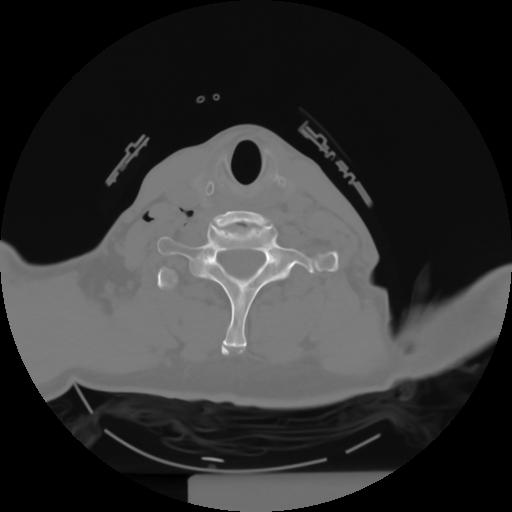

10 P.BLANDAS,,Axial,2.0,P.BLANDAS,,